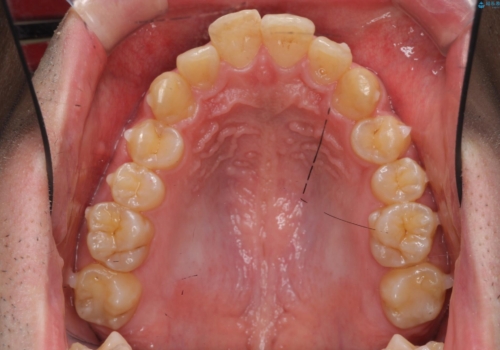

ガタつきの大きい前歯 インビザラインによるマウスピース矯正治療

- ガタつきの目立つ前歯の改善を求めて来院されました。

上顎前突、がたつきを改善すべく上顎臼歯の後方移動・ディスキングを行い歯並びの改善を計画します。

食事・歯ブラシ時以外の時間にしっかりとマウスピースを装着していただけたのでガタつきは大きく改善し良好な歯並びを得ることができました。